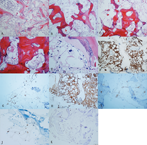

镜下:低倍镜可见部分骨小梁,骨小梁间正常骨髓组织消失,被体积较大的空泡状细胞代替。细胞膜界线清楚,胞质透明或淡红染,部分细胞质内可见嗜酸性透明变性的小球样结构。细胞核大部温和,局灶细胞核可见轻度多形性,核染色质细腻,未见明显异型及核分裂象。部分细胞形似脂肪细胞或脂母细胞,细胞呈片状分布,未见分叶状结构及黏液样间质,局部呈浸润性生长,可见骨小梁哈佛氏管受累;病变区部分骨小梁周围被覆骨母细胞,呈反应性增生改变(病例91图2)。

注:A:低倍镜下部分骨小梁纤细,正常骨髓组织消失;B-D:空泡状细胞代替正常骨髓组织,局部胞质内嗜酸性透明变性的小球样结构,哈佛氏管受累;E:类脂母细胞;F-K:肿瘤细胞广谱CK、EMA、Vimentin、S-100和Brachyury均阳性,Ki67指数较低

免疫组化显示:广谱CK、EMA、Vimentin、S-100和Brachyury均阳性,Ki67指数较低(平均约3%)(病例91图2)。